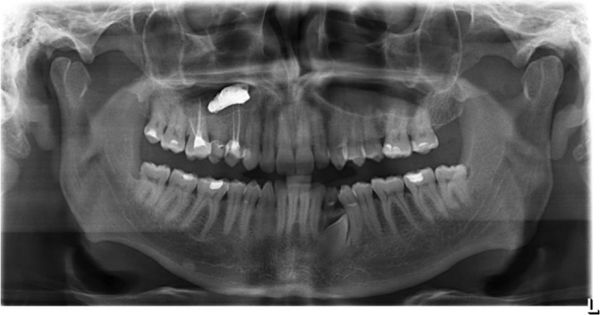

Стандартные рентгенологические методы недостаточно информативны, поскольку они не могут дать объёмную послойную картину черепа, как КТ. На рентгенограммах утолщённая воспалённая слизистая оболочка пазухи имеет серый цвет, участки кальцификатов, которые образуют грибы мицетомы, — белый, а воздух — чёрный. Эти участки характерны только для мицетомы.

Мультиспиральная компьютерная томография остаётся эффективным и единственным способом диагностики мицетомы околоносовой пазухи. Использование трёхмерной реконструкции даёт представление об объёмном взаиморасположении костей, позволяет оценить состояние верхнечелюстной пазухи и зубочелюстной системы (целостность зубов, степень разрушения, цвет, положение в зубном ряду, подвижность, глубину зубодесневых каналов), а при наличии инородных тел точно показывает их форму, размер и местонахождение.

При магнитно-резонансной томографии исследование можно выполнить в двух режимах. С помощью T1-режима в центре поражённой пазухи обычно определяется образование, окружённое слоем жидкости, с низкой интенсивностью сигнала. Такое образование будет тёмным. В режиме T2 МРТ может дать ложноотрицательный результат. При этом режиме грибковое тело имеет низкую интенсивность и выглядит как область, лишённая сигнала, поэтому на снимке может быть принята за воздух.